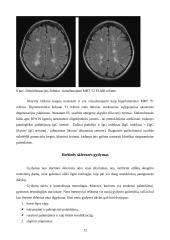

• Išsėtinės sklerozės diagnostika 10